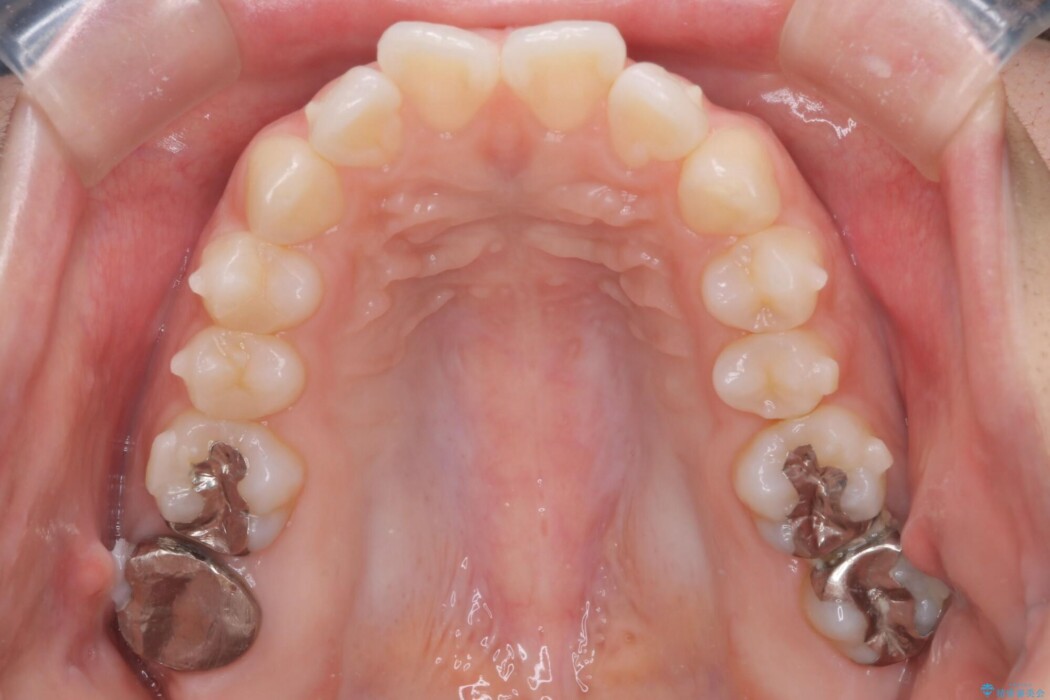

患者様のご希望として抜歯をせずに歯列矯正をしたいとのことでしたので、臼歯部の遠心移動やIPRを行いつつインビザラインを使用した治療を行うこととしました。

今回は非抜歯の矯正治療となりましたので口を閉じた時の口元に大きな変化はありません。